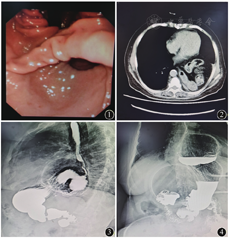

患者女性,82岁,主因胸痛2年伴恶心、呕吐3 d入院。既往高血压、冠心病病史3年,口服药物控制良好,脑梗死病史1年,无后遗症,否认糖尿病史,否认手术外伤史,否认食物、药物过敏史,无烟酒不良嗜好。查体:生命体征平稳,左肺呼吸音低,心率齐,未闻及异常杂音,腹部平坦,全腹软,中上腹轻压痛,无反跳痛,肌紧张(-),肠鸣音4次/min。辅助检查:胃镜:食管裂孔疝、胃扭转?;胸腹部CT示:食管裂孔疝,小肠、胃、网膜、结肠疝入胸腔;上消化道造影:食管裂孔疝(图1,图2,图3,图4)。入院后营养学评分(NRS2002评分)5分,体质指数(BMI)17.2 kg/m2,血常规示血红蛋白85 g/L、白蛋白(ALB)31 g/L,凝血功能及肝肾功能正常。入院后完善心电图、超声心动、肺功能等相关检查,并请心内科及呼吸科评估心肺功能,予患者质子泵抑制剂及适当肠外营养补液治疗1周,患者症状好转后行腹腔镜手术治疗,术中见2/3胃体、网膜、部分空肠、横结肠疝入胸腔,仔细分离疝内容物与疝囊粘连后还纳疝内容物,游离食管及双侧膈肌脚,3-0 Poly缝线间断缝合食管裂孔,再用裁剪成"V"型的双面防粘连合成补片予以加固,最后行胃底前180°(Dor)折叠(图5,图6,图7,图8)。术后患者8 h拔除气管插管,术后第1天拔除胃管嘱患者进食流质,第1~4天予以适量静脉营养支持(补液量按进食情况逐渐减量,保证每日尿量1 000 ml以上),术后第5天出院,随访6个月患者进食量较术前增加1/3,无胸痛、憋气、反酸等症状,体重增加5 kg,血红蛋白117 g/L。

食管裂孔疝(hiatal hernia,HH)是指腹腔内脏器和(或)组织通过食管裂孔进入胸腔所形成的疝,通常认为疝入胸腔的胃体积≥正常胃体积的1/3,或食管裂孔直径超过5~6 cm的HH为巨大食管裂孔疝(giant hiatal hernia,GHH)[1],其主要临床表现为胸痛、反酸、胃灼热、腹胀、憋气、咳嗽等症状,如存在胃扭转可伴有恶心、呕吐、进食困难等表现,而疝内容物一旦出现嵌顿则可引起消化道出血、穿孔或坏死等危及生命的并发症。Carrott等[2]统计120例45~91岁GHH患者的临床症状,其中胃灼热占59%、早饱占54%、呼吸困难占52%、吞咽困难占47%、胸痛占40%、反酸占39%、贫血占37%。不同程度的贫血是食管裂孔疝患者易忽视的,有报道指出,GHH患者中缺铁性贫血的发生率大概为6%~37%,其原因可能为Cameron病变[3]。Cameron病变是一种膈肌或其附近水平胃黏膜慢性线性糜烂病变,由膈肌对疝囊颈压迫,近端胃长期受牵拉和磨损形成,HH患者中Cameron病变的发生率为10%~32%[4]。GHH的诊断通过胸腹部CT、上消化道造影、胃镜等检查多不难诊断,本例患者上消化道造影示:约1/2胃体疝入胸腔,腹部CT提示:结肠、小肠、网膜等一并疝入,符合Ⅳ型巨大食管裂孔疝诊断,同时合并中度贫血及营养不良。